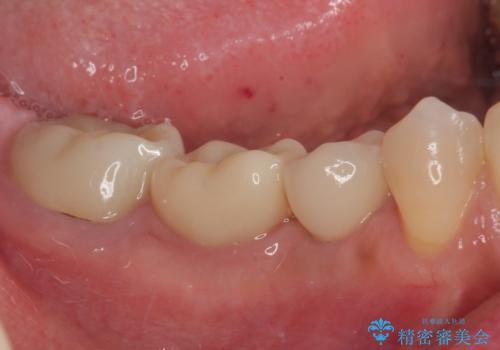

インプラント治療をきっかけに、銀歯を全てセラミックに替えていきました。

人の目を気にせずに、大きく口を開けて笑えるようになりました。